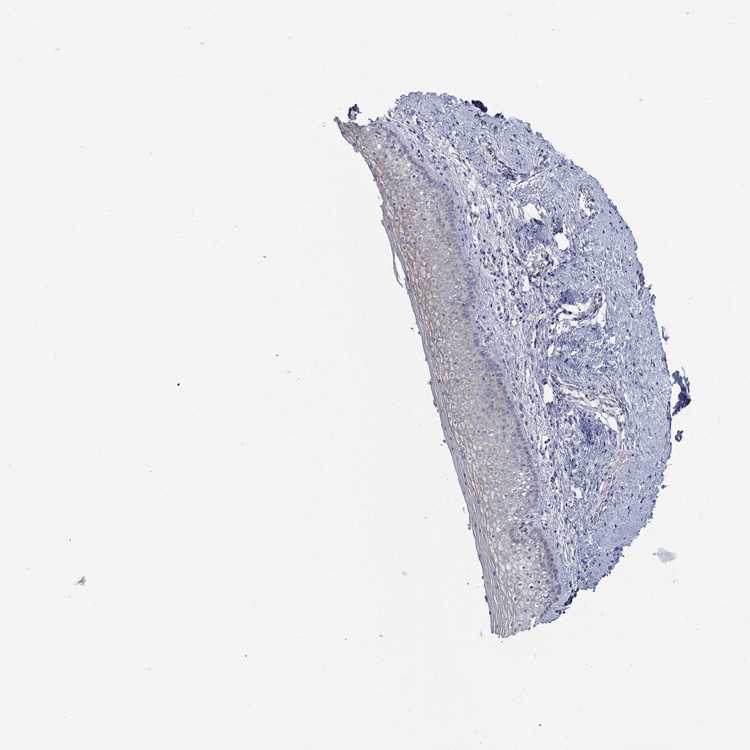

VAGINA - Antibody stainingi

Antibody staining in the annotated cell types in the current human tissue is reported as not detected, low, medium, or high, based on conventional immunohistochemistry profiling in selected tissues. This score is based on the combination of the staining intensity and fraction of stained cells.

Each image is clickable and will lead to virtual microscopy that enables deeper exploration of all samples and also displays staining intensity scores, fraction scores and subcellular localization as well as patient and tissue information for each sample.

Antibody HPA017320

Squamous epithelial cells Not detected